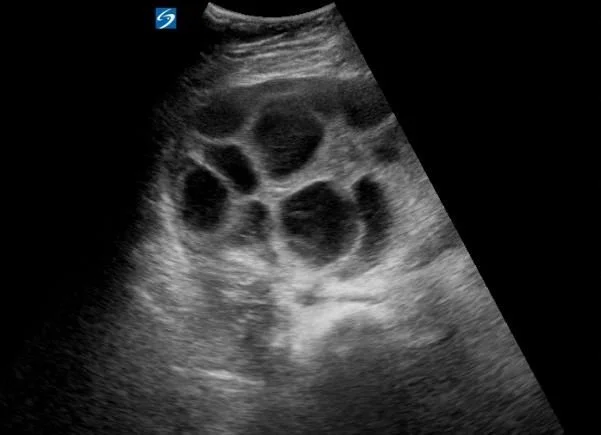

A 22 y.o. woman presented with RLQ pain and ascites.

An US was done in the ED

Hint: the pt is receiving LH injections as part of her infertility treatment.

Our patient had ovarian hyperstimulation syndrome caused by her fertility treatments and presented with ascites and pain.

The problem occurs when greater than 20 follicles are produced. Large volumes of ascites can be produced because of  increased capillary permeability( increased vascular endothelial growth  factor)  causing pain, respiratory distress and oliguria. If the volume of ascites is large enough, pleural effusions develop.  Complications of renal failure and DVT can also result.  About 2% of patients that receive drugs to stimulate the ovaries develop ovarian hyperstimulation. The  risk factors  include: polycystic ovaries, high follicle count and elevated serum estradiol. Stimulation protocols using hCG for luteal phase support also increase the risk.